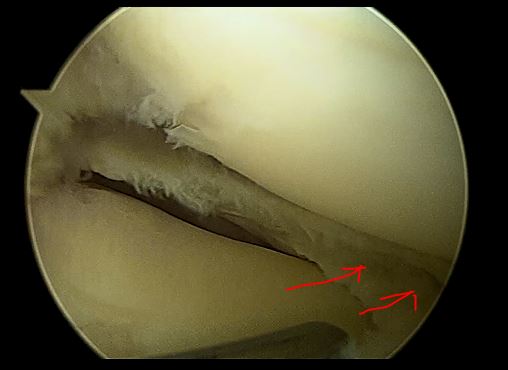

1,女性,14 岁,右膝关节弹响,膝关节交锁。关节镜下见外侧完全盘状半月板 ,予关节镜下成形术!

半月板为盘状,大而厚,完全覆盖胫骨平台

使用蓝钳等关节镜器械,修整半月板,切除中央部

盘状半月板成形后为正常的“半月”形